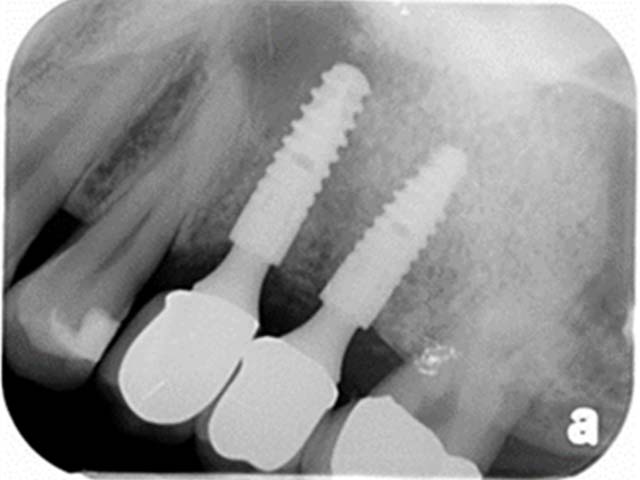

鼻竇增高術(側窗) 首頁 案例分享 人工植牙 鼻竇增高術(側窗) 鼻竇增高術(側窗) 製作多年的牙橋,牙根斷裂,發炎 鼻竇增高術 側面開窗 抬高鼻竇 鼻竇增高術 置入骨粉 覆蓋再生膜,保護骨粉 術後追蹤,傷口良好 裝戴正式假牙 完成 8年追蹤 左上牙根斷裂 植牙重建 九年追蹤